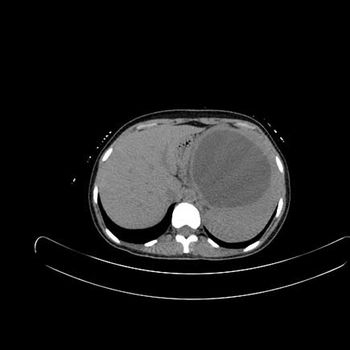

Case History: A 33-year-old patient presented with history abdominal discomfort for 5 months.